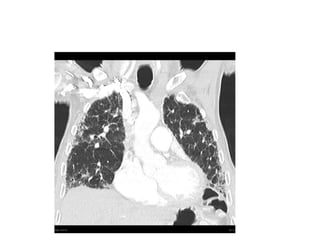

Interstitial Lung Disease – A quick

guide

• Umbrella term.

• Consider:

• 1) Idiopathic interstitial pneumonias of which

usual interstitial pneumonia is commonest type

(also known as idiopathic pulmonary fibrosis)

• 2) Interstitial lung disease of known cause –

connective tissue disease, drug related, dusts

which may be organic or inorganic.

• 3) Granulomatous interstitial lung disease –

sarcoidosis.

Interstitial Lung Disease– A quick guide • Umbrella term. • Consider: • 1) Idiopathic interstitial pneumonias of which usual interstitial pneumonia is commonest type (also known as idiopathic pulmonary fibrosis) • 2) Interstitial lung disease of known cause – connective tissue disease, drug related, dusts which may be organic or inorganic. • 3) Granulomatous interstitial lung disease – sarcoidosis.